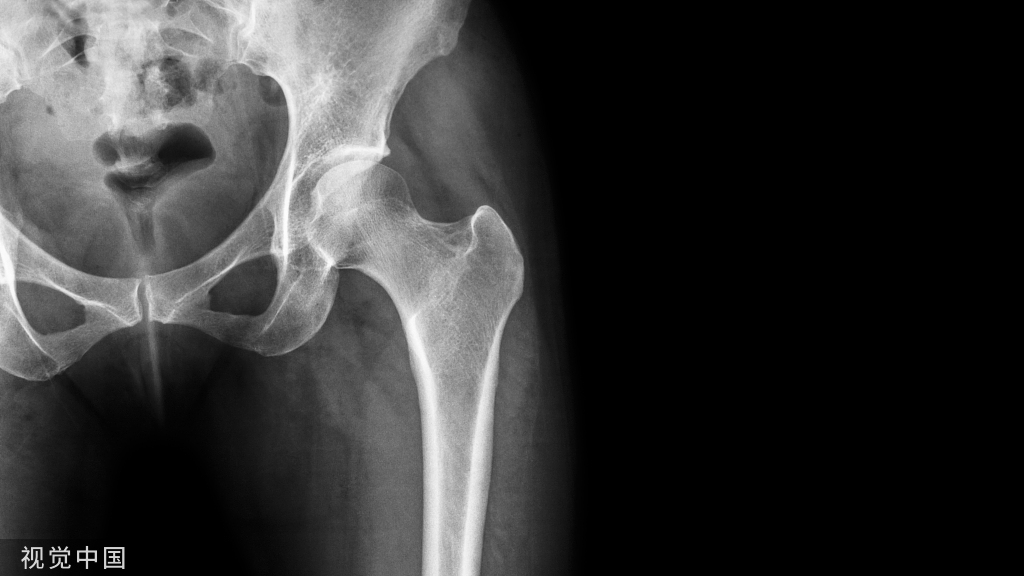

髋关节后脱位往往合并股骨头骨折(5-15%)。最早(1957年)由Pipkin描述并分类,因而被命名为Pipkin骨折。

入路需根据骨折类型,还要考虑股骨头血运保护问题,以防术后头坏死(如下图)。